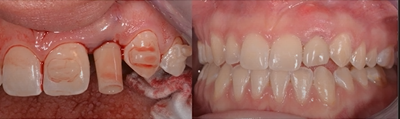

Figure 10 shows a classic high-risk esthetic case. A 19-year-old female patient with a thin gingival biotype presented with a congenitally missing tooth No. 10. She had previously undergone clear aligner therapy to improve the esthetics of her teeth to the extent possible. The clinician discussed options with her: a bonded Maryland Bridge, a three-unit fixed prosthesis, or implant placement. The patient desired a dental implant with an immediate provisional. It was decided that placement of an implant would require a hybrid workflow-ie, analog technology as well as digital technology using dynamic navigation. Figure 11 shows an imaging guide that can be used in such a case, as well as a virtual tooth.

To measure accuracy, the clinician superimposed the plan on the postoperative CT scan and then measured the difference with software. This case had an angular deviation of 3.1°, a platform deviation of 0.81 mm, and an apical deviation of 0.45 mm-all of which were within acceptable parameters.

Figure 12 shows the temporary abutment (left panel) after the implant and connective tissue graft were placed, and the patient 2 weeks postoperatively (right panel). Seven years later, the restoration remains sound (Figure 13).

Fig 10. Patient with congenitally missing tooth No. 10.

Fig 11. Virtual tooth and imaging guide that were used for planning in this patient with the congenitally missing tooth No. 10.

Fig 12. Left panel: temporary abutment in the patient with the congenitally missing tooth No. 10. Right panel: Two weeks postoperatively after the implant and connective tissue graft placement. (Images courtesy of Dr. Keith Progebin.)

Fig 13. Patient with congenitally missing tooth No. 10 at 7 years postoperatively.